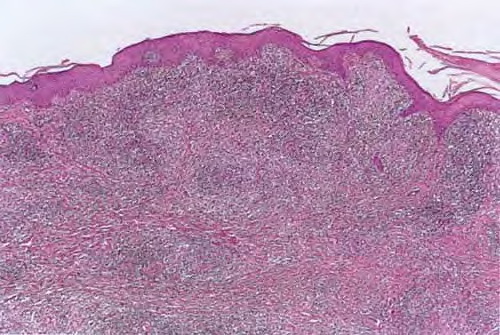

Sporotrichosis =داء الشعريات المبوغة